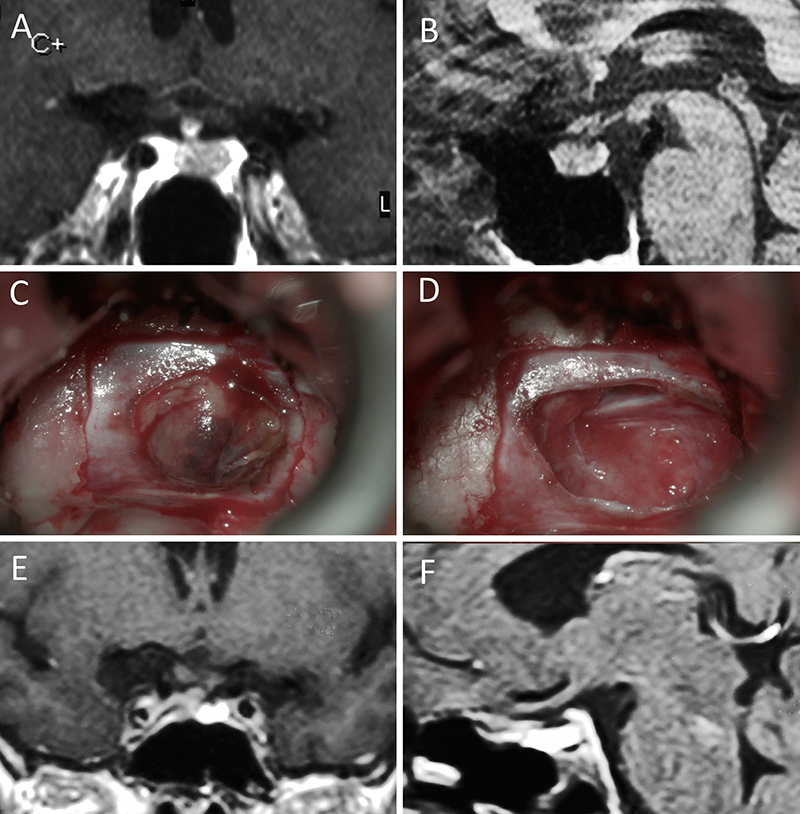

Figura 5: Apoplejía hipofisaria hemorrágica en un hombre de 32 años. El paciente presentó cefalea y parálisis completa del III par. Tuvo restitutio ad integrum en el seguimiento. A-B: RM preoperatoria; C-D: intraoperatorio; E-F: RM postoperatoria.

Figura 6: Apoplejía hipofisaria hemorrágica en un hombre de 55 años. El paciente presentó cefalea, déficit visual y parálisis completa del III par. Evolucionó favorablemente tras la cirugía, revirtiendo el cuadro. A-B: RM preoperatoria; C-D: intraoperatorio; E-F: RM postoperatoria.